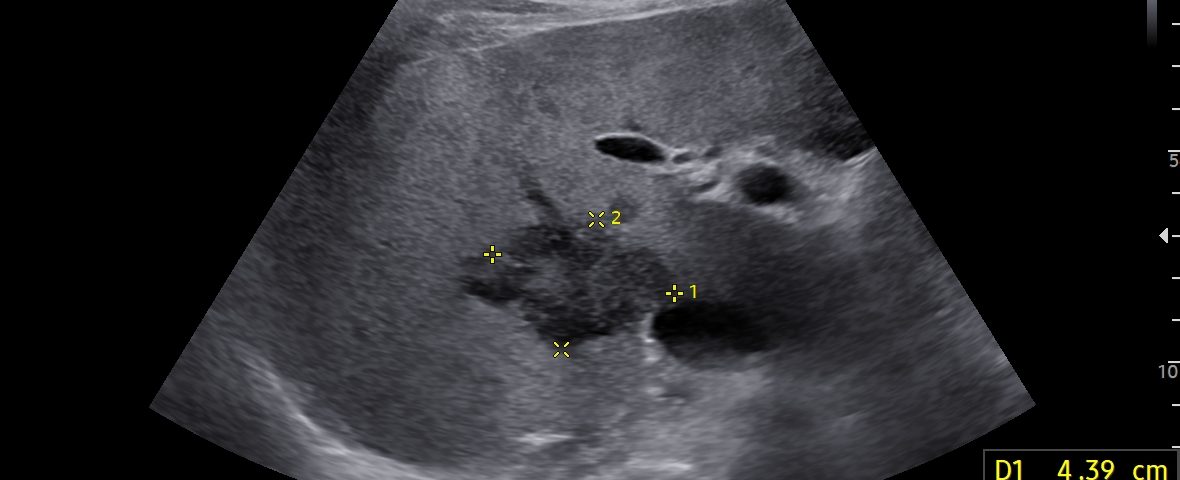

VIDEO 1: On CEUS (Video 1), the lesion exhibited early peripheral rim-like enhancement in the arterial phase, followed by centripetal filling with persistent non-enhancing central areas, likely representing necrotic foci. Washout occurred within one minute, suggesting a cholangiocarcinoma component, either alone or in combination with a hepatocellular component.

On CEUS (Video 1), the lesion exhibited early peripheral rim-like enhancement in the arterial phase, followed by centripetal filling with persistent non-enhancing central areas, likely representing necrotic foci. Washout occurred within one minute, suggesting a cholangiocarcinoma component, either alone or in combination with a hepatocellular component.

Panoramic imaging was subsequently performed: a CT scan followed by MRI confirmed the suspicion of malignancy, without evidence of biliary dilatation or vascular invasion (Figs. 3 and 4); however, a definitive diagnosis could not be established.